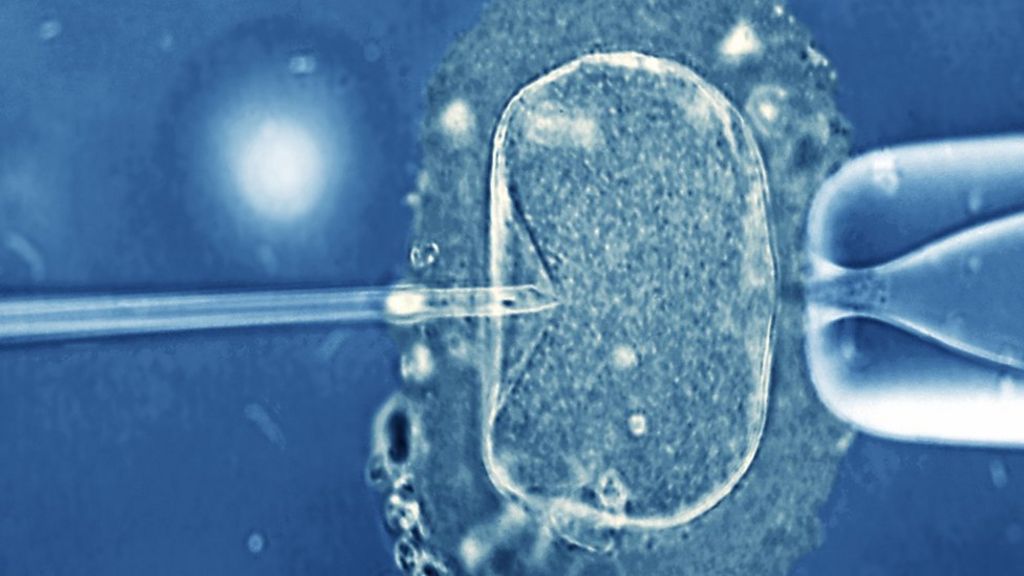

Boys born to fathers who needed help conceiving have poorer sperm quality as adults than peers conceived without help, a study suggests.